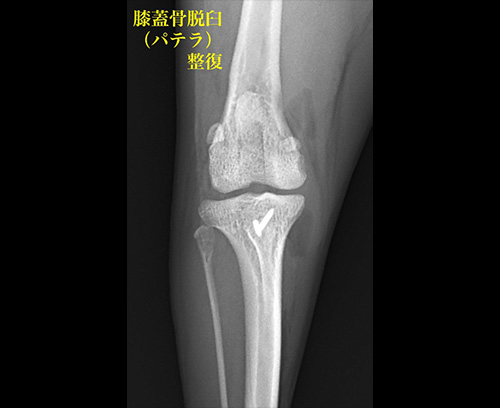

膝蓋骨(パテラ)脱臼

膝蓋骨脱臼